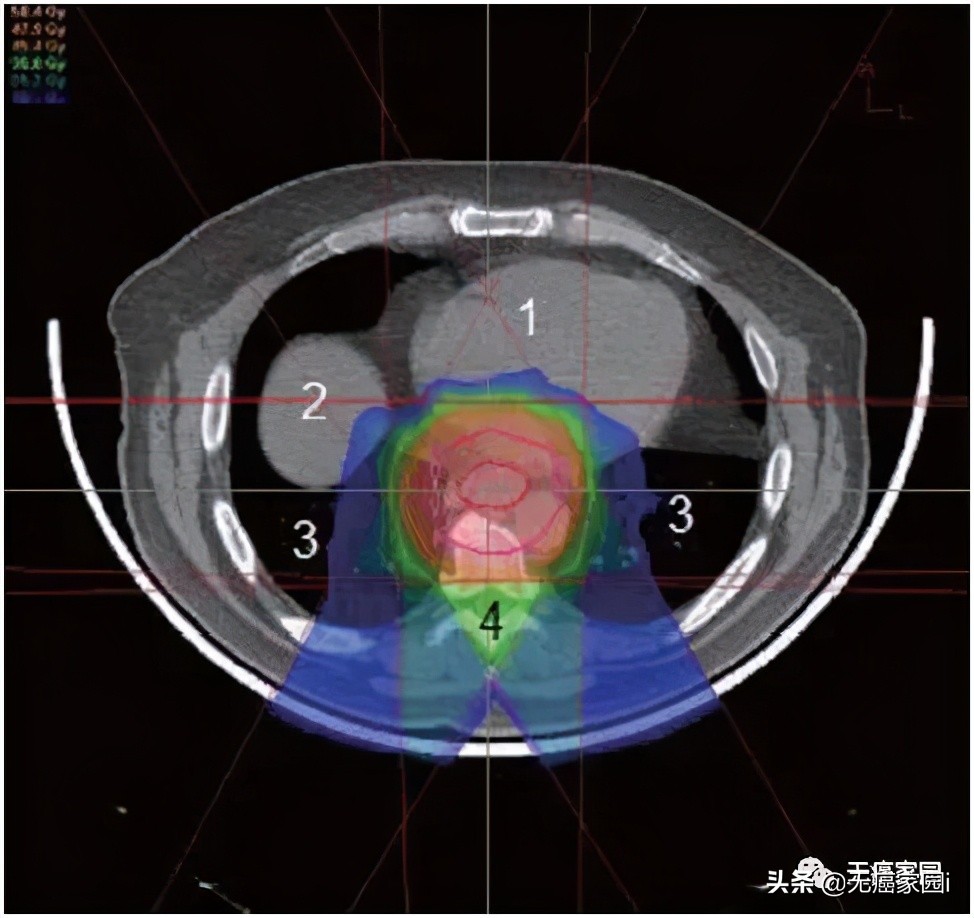

食道位于后纵隔内,靠近几个关键结构,即肺、脊髓和心脏。最大限度地减少对这些关键结构的毒性降低了患者的整体治疗发病率和死亡率。然而,必须在放射野中考虑足够大的边缘以覆盖肿瘤区域和受累淋巴结,这使周围器官面临更大的风险。肺剂量是食管癌放射期间毒性的主要危险因素。为了将脊髓剂量保持在容许范围内,通常需要使用多个倾斜角度的光束(图1~3)。这就导致肺部接收到大量辐射剂量,从而产生放射性肺炎和术后肺部并发症。

图1:治疗食道的后斜质子束的轴向视图。到达食道后,剂量立即下降,这最大限度地减少了心脏和肺接受的辐射剂量;1. 心;2. 肝脏;3. 肺;4. 脊髓